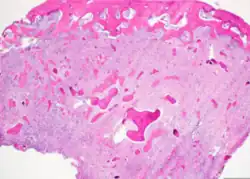

Cemento-ossifying fibroma is a well-demarcated lesion, often encapsulated by a thin fibrous capsule and sharply separated from adjacent normal bone. It shows significant internal variation, with differing amounts of fibrous and mineralized tissue—even within the same lesion. Mineralization is often more prominent centrally and typically includes osteoid, woven to lamellar bone, and dense basophilic cementum-like calcifications. Bony trabeculae may fuse into broad sheets or form thick, anastomosing strands. Osteoblastic rimming is commonly seen around bone trabeculae.[27]

The stroma is fibroblastic and may exhibit areas of hypercellularity and nuclear hyperchromasia; however, mitotic activity is rare and cellular atypia is minimal .[28] The mineralized component may include acellular or paucicellular cementum-like spheres along with bone structures .[28]

Though rare, hemorrhagic cystic degeneration—resembling aneurysmal bone cyst formation—can occur, more commonly in juvenile variants.[27][29] Histological overlap can exist among subtypes: psammomatoid and trabecular JOF may exhibit features resembling COF, and vice versa. In syndromic cases, such as gnathodiaphyseal dysplasia, COF lesions appear more fibrous with basophilic, acellular bone droplets and spherical ossicles, but histologically resemble nonsyndromic counterparts .[30]

Histologically, COF comprises a fibrocellular stroma with varying degrees of ossification, including trabecular or lamellar bone and cementum-like material.[35] Differentiation from other fibro-osseous lesions—such as fibrous dysplasia and cemento-ossifying fibroma—requires histopathological assessment.[36]